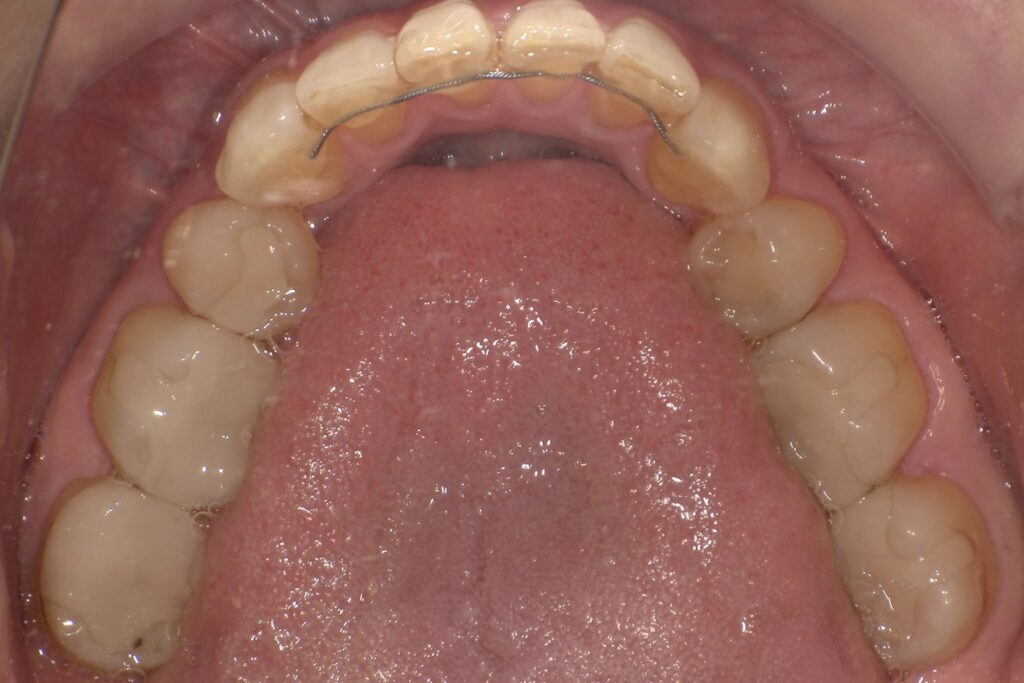

固定式リテーナー(固定保定)

前歯の裏側にワイヤーを接着剤で固定するタイプです。

主に下の前歯に使われ、見た目には全くわかりません。

取り外しの必要がないため装着忘れがなく、長期的な保定に有効ですが

歯石がつきやすい、舌に対する違和感、外れてしまった時に気づかない、虫歯になりやすいなどのリスクがあります。